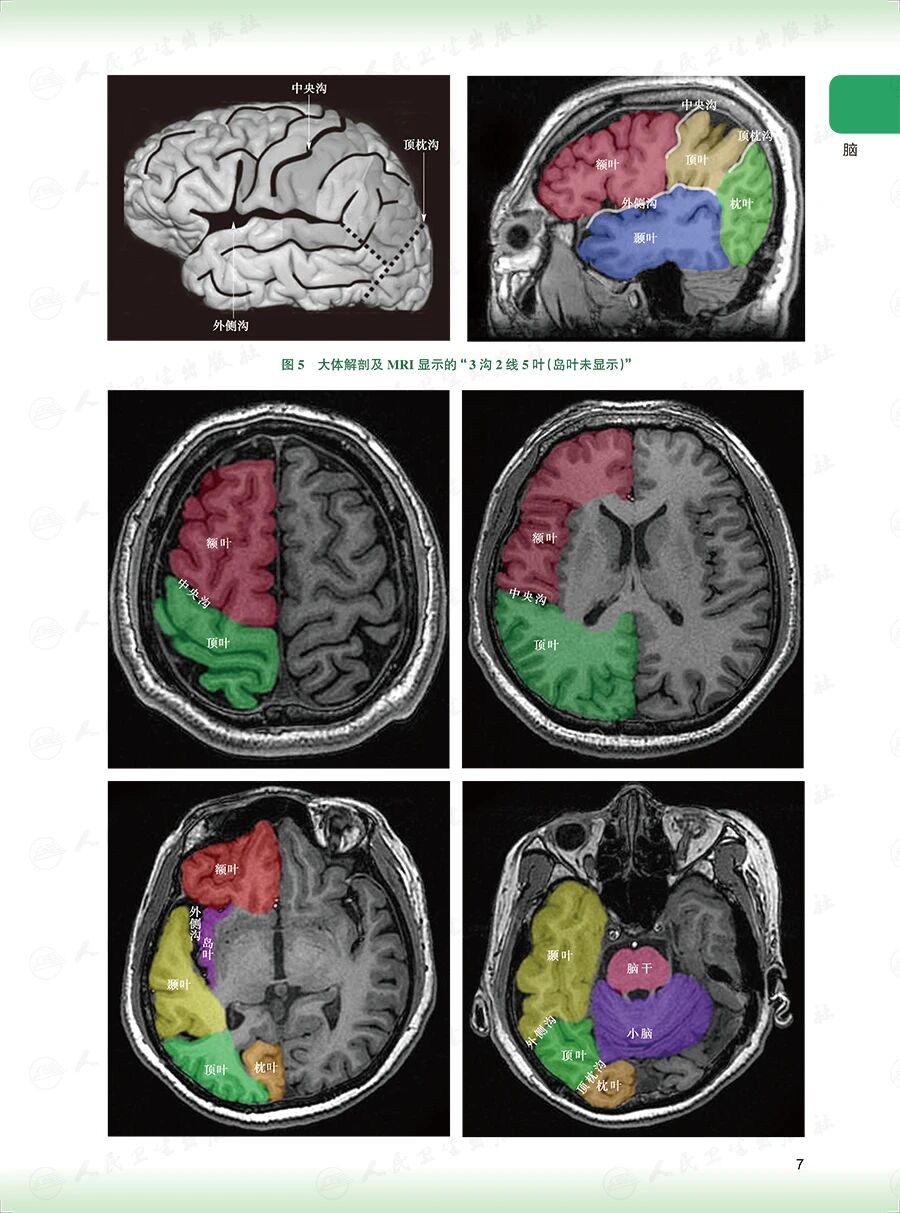

《头颈部放射治疗解剖图谱》

——破译头颈部靶区勾画的解剖密钥

样章试读